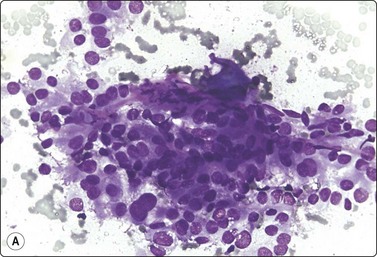

Primary adrenal cortical tumors17-19,120,121

Criteria for diagnosis

Moderately to highly cellular smears,

Microarchitecture varies from tissue fragments with prominently vascular stroma to loose clusters or sheets of cells, to single cells, in variable proportions,

Abundant granular, sometimes vacuolated, cytoplasm; indistinct cell borders; many stripped nuclei; small lipid droplets,

Nuclei generally eccentric, rounded, variably enlarged; anisokaryosis, pleomorphism and atypia variable,

High cellularity, necrosis, nuclear pleomorphism, abnormal chromatin, mitoses, prominent nucleoli and large tumor size are indicative of malignancy,121

Melan A (A103) and inhibin usually positive, cytokeratin (AE1/AE3) often negative.122,123

Most cortical adenomas subjected to FNB are asymptomatic lesions detected by abdominal CT in the preoperative investigation of patients with potentially resectable lung tumors, or incidentally by abdominal CT for other reasons (‘incidentaloma’). The main purpose of FNB is to exclude metastatic cancer. Smears are moderately cellular. The cells are poorly cohesive and appear single, in groups and in loose monolayered sheets without a distinctive architectural pattern. There are numerous stripped nuclei with a background of lipid droplets, but some cells have an abundant granular and vacuolated cytoplasm (Fig. 12.32). Lipofuscin pigment may be seen. The nuclei are generally small and uniformly round and have one or several small nucleoli, but anisokaryosis can be prominent in some tumors. Nuclear chromatin is granular and evenly distributed. Saboorian et al.17 emphasize the importance of precise positioning of the needle at biopsy since cells of an adenoma are not easily distinguished from those of normal adrenal cortex.

As in other endocrine tumors, the cytological pattern is not a good predictor of biological behavior and features overlap between adenoma and adrenal cortical carcinoma. Tumor size is an important parameter. In general, adenomas are less than 3–4 cm in diameter, carcinomas over 5 cm.21,121 Cells of well-differentiated adrenal cortical carcinoma to a variable degree resemble those of cortical adenoma, whereas cells of poorly differentiated carcinomas display severe nuclear pleomorphism, abnormal nuclear chromatin and very large nucleoli (Figs 12.34 and 12.35). Ren et al.,121 in an analysis of 20 cases, found high cellularity, necrosis, nuclear pleomorphism, mitoses and prominent nucleoli to be the most useful indicators of malignancy. Clinical, radiological and immunocytochemical findings must be correlated with the cytology.